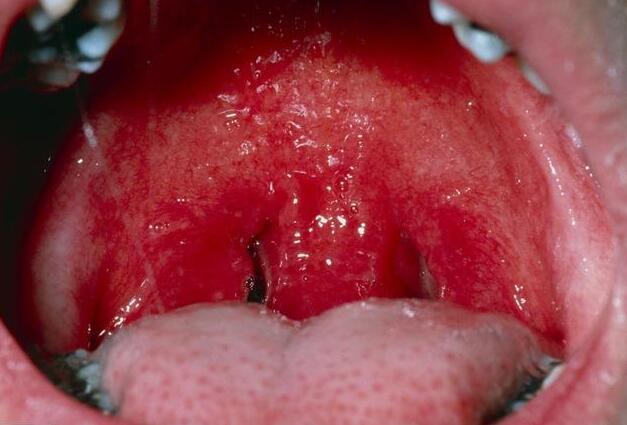

慢性咽炎,这个听起来并不严重的疾病,却让无数人苦不堪言。据统计,我国约有60%-70%的人患有不同程度的咽炎,甚至有“十人九咽”的说法。为什么这种疾病如此普遍,又为何总是反复发作?让我们从慢性咽炎的“慢性”特性入手,一探究竟。

慢性咽炎的“慢性”特性,正是其反复发作的关键所在。与急性咽喉炎不同,慢性咽炎是一种持续时间长、症状顽固的疾病。它的病程通常超过3周,甚至可能持续数月或数年。这种长期的炎症状态,使得咽部黏膜处于持续的刺激和损伤之中,难以完全恢复。

那么,慢性咽炎与急性咽喉炎究竟有何本质区别?首先,从病因来看,急性咽喉炎多由病毒或细菌感染引起,而慢性咽炎则更多是由长期的非生物因素刺激所致,如长期用嗓过度、经常进食辛辣刺激的食物、吸入有害气体或工业粉尘等。其次,从症状上看,急性咽喉炎的症状较为剧烈,如剧烈的喉咙痛、发热等,而慢性咽炎的症状则相对温和,但更为持久,如喉咙干燥、灼热、异物感等。最后,从病程来看,急性咽喉炎通常在数天至数周内可以治愈,而慢性咽炎则可能反复发作,难以根治。